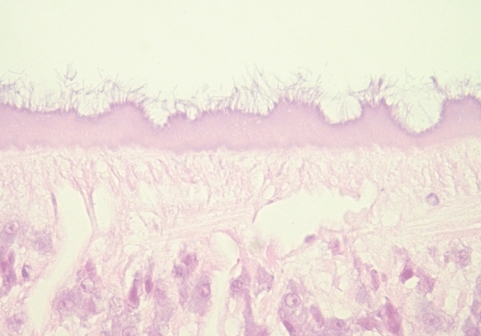

Longitudinal sections of the worm were prepared and stained with hematoxylin and eosin (Figs. 2, 3). Morphological observation was performed by light microscopy, and measurements of internal organs were done with a computer-aided image analysis system (analySIS, SIS GmbH, Duisburg, Germany). Testes were roughly triangular in shape (Fig. 3A). They were tandem and separated by the posterior part of the uterus. The anterior testis was more triangular and situated in the posterior part of the middle one-third body, measuring 420 × 560 µm. The posterior testis, crescentic and anteriorly concave, was located in the anterior part of the posterior one third, 340 × 620 µm. The ovary, triangular and 150 × 150 µm, was placed apart from the median line between the cirrus pouch and posterior testis. The cirrus pouch, oval and 380 × 230 µm, was situated anterolaterally to the ovary. Some part of the uterus, egg containing, was located between the anterior and posterior testes. Vitellaria, follicular, were distributed from the post-acetabular level to the posterior end of the body along the lateral margins. Intestinal ceca bifurcated and ran posteriorly. They contained a lot of host red blood cells and pigments stained in brown and black color (Fig. 3B). The undigested cells were abundant mainly in the posterior portion of the ceca. The pigments were found in clusters adhering to the luminal surface of gastrodermis as well as lying free and mixed with remnants of undigested red blood cells in the lumen. No tegumental spine was noticed. The outer surface of the tegument, however, was occupied by numerous filamentous materials (Fig. 4). Their size and distribution was variable along the body. From these findings, the present worm was identified as Clinostomum complanatum.

The nutrition of Clinostomum has been studied, but, in general, it is restricted to glucose uptake across the external surface. Consequently, only a limited amount of information is available regarding the oral uptake. According to the histological study, the oral sucker of Clinostomum engulfs the mucous layer of the throat or mouth of bird hosts, and the intense liquefactive necrosis of engulfed tissue occurs [11]. In the present case, petechial hemorrhage was observed endoscopically after the removal of the parasite. Histological observation on the ceca of the worm revealed numerous blood cells and fine granules of the brown-black pigment in the lumen in contact with the gastrodermis. The pigment looked like a degradation product of hemoglobin by digestive process. Thus, it is suggested that C. complanatum could feed on blood extracted from the mucosa and cause mucosal hemorrhage due to attachment injury.

Fig. 3

Histological sections of C. complanatum obtained from the patient. (A) Typical distribution of the main reproductive organs. C, cirrus pouch; O, ovary; Ta, anterior testis; Tp, posterior testis. H-E stain, × 40. (B) An enlarged view of the cecum showing ingested blood cells and numerous fine granules of the brown-black pigment. H-E stain, × 200.

Fig. 3 Histological sections of C. complanatum obtained from the patient. (A) Typical distribution of the main reproductive organs. C, cirrus pouch; O, ovary; Ta, anterior testis; Tp, posterior testis. H-E stain, × 40. (B) An enlarged view of the cecum showing ingested blood cells and numerous fine granules of the brown-black pigment. H-E stain, × 200.